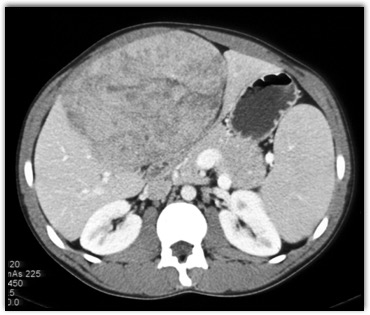

In this teenager the best diagnosis is?

CTisus Quiz   CTisus Quiz

FNH

hepatic adenoma

angiosarcoma of the liver

hepatoblastoma